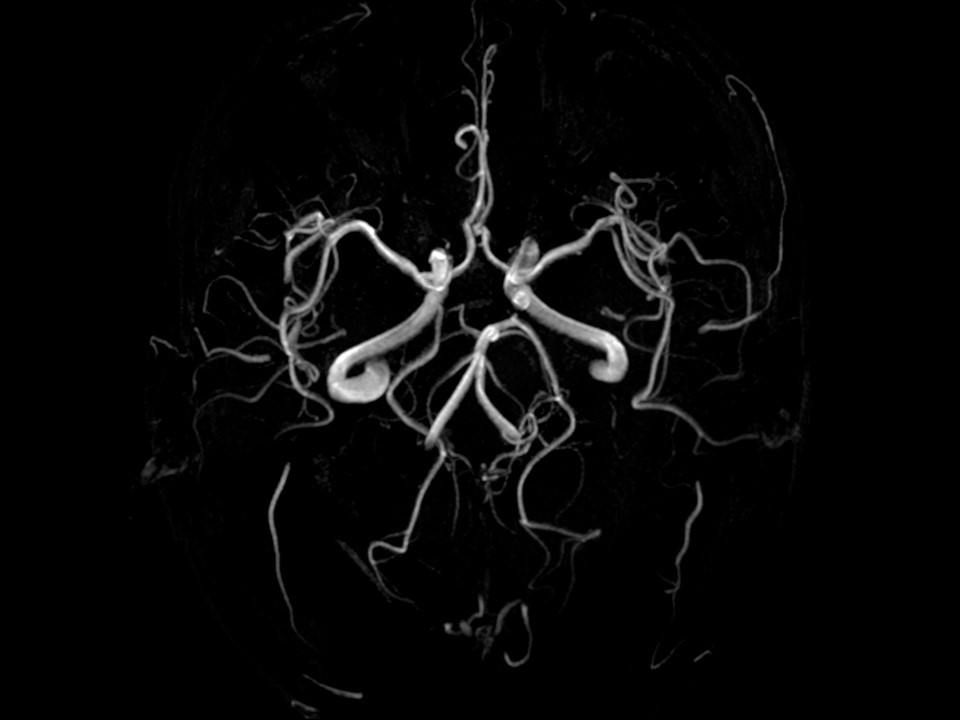

| Cộng hưởng từ 1.5 tesla | Cắt lớp tỷ trọng đa dãy đầu thu |

| - MRI không tiêm thuốc đối quang từ với các tất cả các bộ phận(sọ não, ổ bụng, tiểu khung, cột sống, chi, khớp…). - MRI có tiêm thuốc đối quang từ với hệ thống tiêm máy. - MRI hệ mạch máu - MRI tầm soát toàn thân với phần mềm chuyên dụng | - Chụp cắt lớp không tiêm thuốc cản quang với tất cả các bộ phận(sọ não, ổ bụng, tiểu khung, cột sống, chi, khớp…).. - Chụp cắt lớp có tiêm thuốc cản quang với hệ thống tiêm máy. - Chụp cắt lớp hệ mạch - Chụp cắt lớp nội soi ảo đại tràng, phế quản, xoang. - Chụp cắt lớp đánh giá tưới máu não - Chụp cắt lớp dựng hình 3D hệ thống xương, hàm mặt, HTN… |